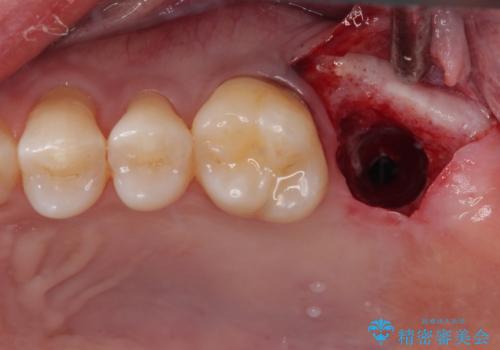

根尖病巣も大きかったため先に抜歯を行い、1ヶ月後にインプラントを埋入しました。

インプラントの埋入から被せものの装着まで2ヶ月で終えることができました。治療期間も短く、しっかり咬めるため大変喜んでいただきました。